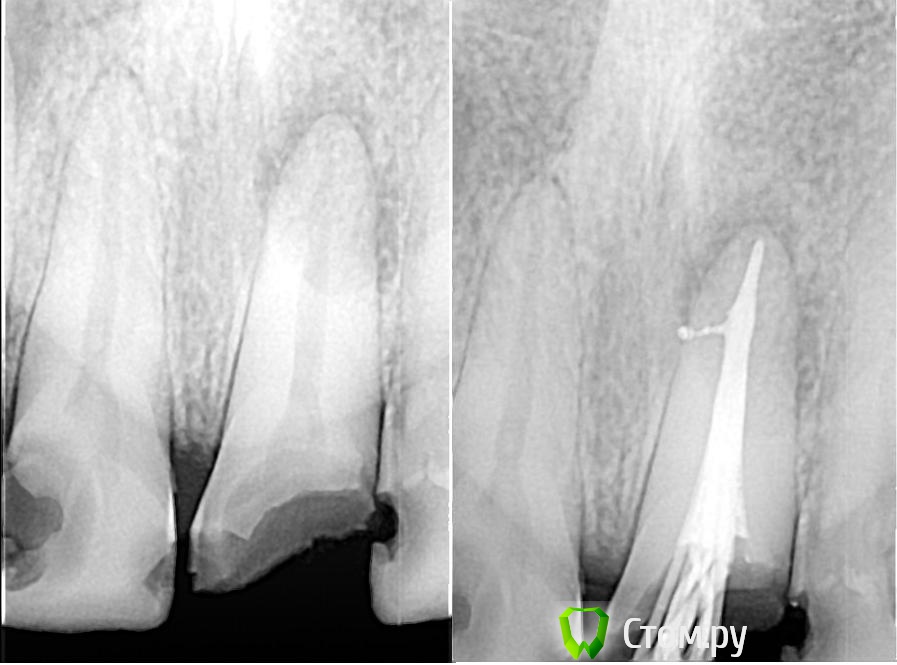

SatoSan Опубликовано 21 ноября, 2014 Поделиться Опубликовано 21 ноября, 2014 Критика приветствуется. Хронический периодонтит, первичное эндо. 6 Ссылка на комментарий

M@estro Опубликовано 21 ноября, 2014 Поделиться Опубликовано 21 ноября, 2014 Пока нечего критиковать. Снимок класс . Кофф где на снимке ? Снимок бы месяца через три , но верю,что всё будет окей Ссылка на комментарий

Shaid Опубликовано 21 ноября, 2014 Поделиться Опубликовано 21 ноября, 2014 У меня тоже большая уверенность, что заживление на реколле мы увидим. Ссылка на комментарий

SatoSan Опубликовано 21 ноября, 2014 Автор Поделиться Опубликовано 21 ноября, 2014 Пока нечего критиковать. Снимок класс . Кофф где на снимке ? Снимок бы месяца через три , но верю,что всё будет окей Снимки сам делаю вроде бы проекция ничего, а вот четкость мне кажется может быть лучше (визиограф Денталикс). По поводу контроля так это вряли. Геологи... Хоть бы на реставрацию пришел. Там периодонтитов ну штук 10 не меньше, но волновал его именно 21") С коффером войдем в новый год! Вот вот уже отпуск выберусь приобрету. 2 Ссылка на комментарий